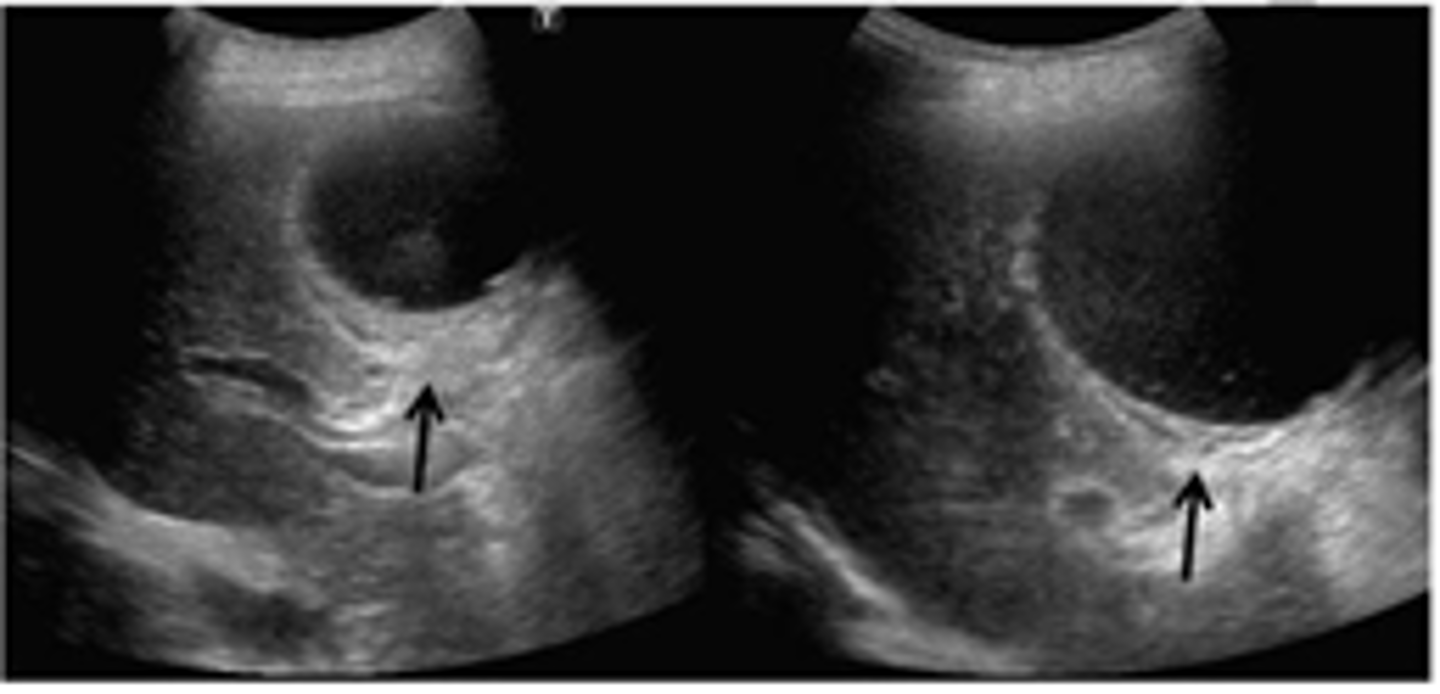

Cholelithiasis sonographic findings

- mobile, echogenic structure within GB lumen that produces posterior shadowing

-WES sign if completely filled with stones

-change in patient position that shows movement

-some stones may adhere to the wall and not cause shadow- twinkle artifact may be used to differentiate b/w a small stone and polyp:

-twinkle occurs posterior to a strong, granular surface like crystals or calcifications